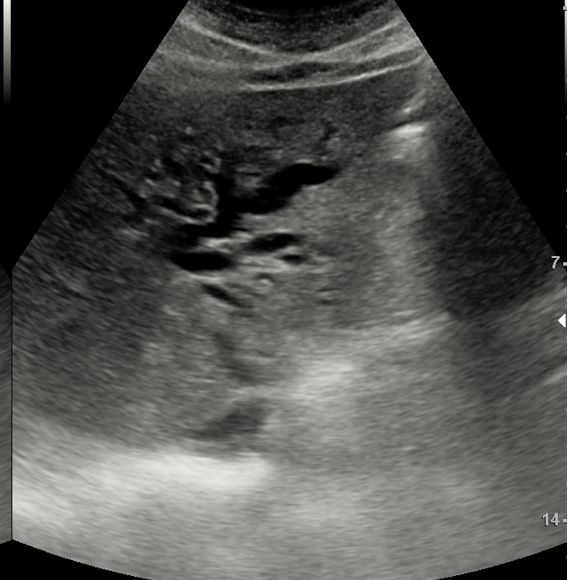

Hallazgos ecográficos

JC: Tumor páncreas.

Diagnóstico definitivo: Adenocarcinoma de cabeza de páncreas cT1c cN0 cM0 KRAS G12D.

Recuperada tras intervención quirúrgica y con buena tolerancia a la quimioterapia.En este caso se observa la importancia de una buena formación en ecografía clínica para la realización de hallazgos de patología maligna en situaciones de sospecha. Así como el poder descartar otros diagnósticos e incluso patología urgente.